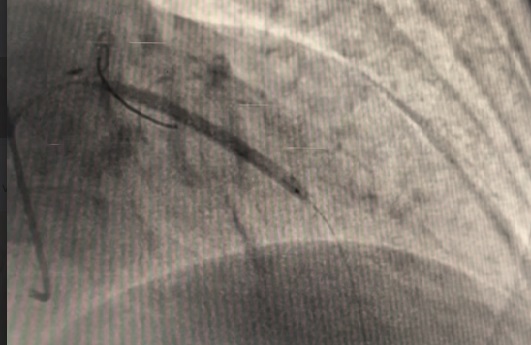

The LM had 50% ostial stenosis. LAD showed proximal CTO with bridging collaterals from the right coronary artery. LCx demonstrated proximal CTO with contralateral collaterals from the RCA. The right coronary artery was dominant with mild disease. The case represented complex dual CTO with LM involvement, posing both technical and procedural challenges due to tortuosity and calcification.

A dual access strategy was used: right radial for RCA and right femoral for LCA. For LCx CTO PCI, a Finecross microcatheter (Terumo, Japan) was advanced to the distal LCx. Predilation was done using a 2.5 ¡¿ 15 mm Firefighter balloon (Medtronic, USA) at 8 atm, followed by stenting with a 3.5 ¡¿ 30 mm Orsiro Mission drug-eluting stent (Biotronik, Germany) at 16 atm. Postdilation was performed with a 3.0 ¡¿ 15 mm Accuforce non-compliant (NC) balloon (Terumo, Japan) at 14 atm.For LAD CTO PCI, Finecross with Fielder wire (Asahi, Japan) failed to cross; Gaia First (Asahi, Japan) successfully reached the distal LAD. Predilation was performed using NC Sapphire 24 (OrbusNeich, Hong Kong) 3.5 ¡¿ 12 mm and Wedge NC (Boston Scientific, USA) 3.0 ¡¿ 15 mm. A 3.0 ¡¿ 40 mm Biofreedom Ultra stent (Biosensors, Singapore) was deployed at 14 atm. Proximal dissection into LM was noted, requiring LM–LAD stenting with 3.5 ¡¿ 22 mm Orsiro Mission and proximal optimization technique (POT) using 4.5 ¡¿ 18 mm NC Emerge balloon (Boston Scientific, USA). Intravascular ultrasound (IVUS) revealed ostial–proximal LCx disease, confirming a bifurcation lesion. Ostial LCx was predilated with a 3.5 ¡¿ 12 mm NC Sapphire balloon and stented with a 3.5 ¡¿ 14 mm Biofreedom Ultra. Final kissing balloon inflation was done with NC Sapphire 3.5 ¡¿ 12 mm (LAD) and 3.5 ¡¿ 14 mm (LCx), followed by final POT with NC Emerge 4.5 ¡¿ 8 mm balloon at 18 atm. Final shot revealed TIMI 3 flow with no dissection or perforation.